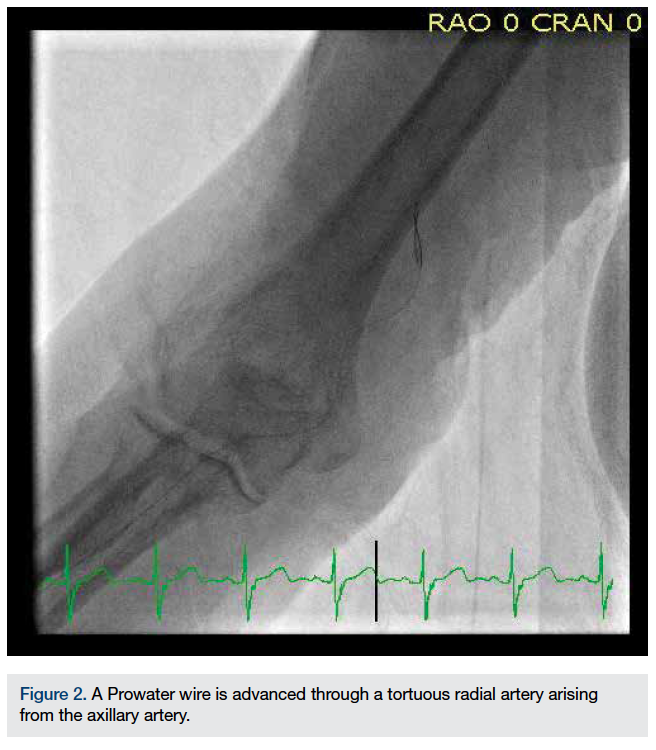

A 6 French Amplatz Left (AL) 2 guide was used to cannulate the SVG to the RCA. Additional heparin was used for weight-based anticoagulation. After deploying a 5 mm Spider filter (ev3) in the SVG to the RCA, a 4.0 x 26 mm Integrity bare-metal stent (Medtronic) was deployed by direct stenting, with a good final angiographic result (Figure 4).